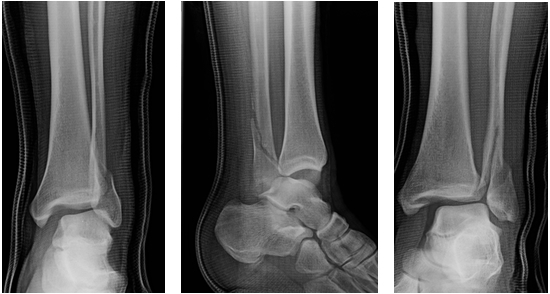

Describe this fracture?

A

BOSWORTH

- Fracture-dislocation of the ankle resulting in the fibula being entrapped behind the tibia

- Produced by severe external rotation force applied to the foot; physical examination reveals foot severely externally rotated in relation to the tibia